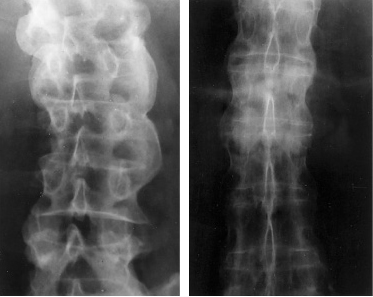

7- Slip Disc.

Slipped disc can be the consequence of an injury or trauma faced by your neck. Due to a slipped disc your spinal cord is pressured ultimately resulting in a stiff neck.

8- Ankylosing Spondylitis.

It is a type of arthritis that affects the joints of your spine and this also results in back and neck pain.